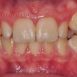

Interdisciplinary Treatment of Patients with Deep Overbite and Parafunctional Activity

Bruxism is defined as parafunctional grinding of teeth and due to the excessive wear of the posterior teeth, patients with long-standing bruxism often have pathological deep overbite. For many decades, treatment of bruxism and deep overbite was focused on reshaping the bite for achieving an occlusion free of deviations. Despite large efforts, the management of bruxism and subsequent deepening overbite was not obtained.